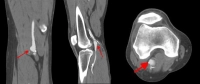

Generell wird ab einer Aneurysma-Größe von 2 cm eine Operation empfohlen, da auch kleine Aneurysmen häufig symptomatisch werden können. Bei fehlenden Fußpulsen und Aneurysmen kleiner als 2 cm mit partieller Wandthrombosierung können „stille“ Embolisationen auftreten, weshalb bei dieser Konstellation die OP-Indikation individuell gestellt werden muss.

Akute und chronisch-kritische Ischämien, lokale Druckfolgen, venöse Thrombosen durch Kompression, septische Aneurysmen und Ruptur stellen unabhängig von Ausdehnung oder Durchmesser eine OP-Indikation dar.